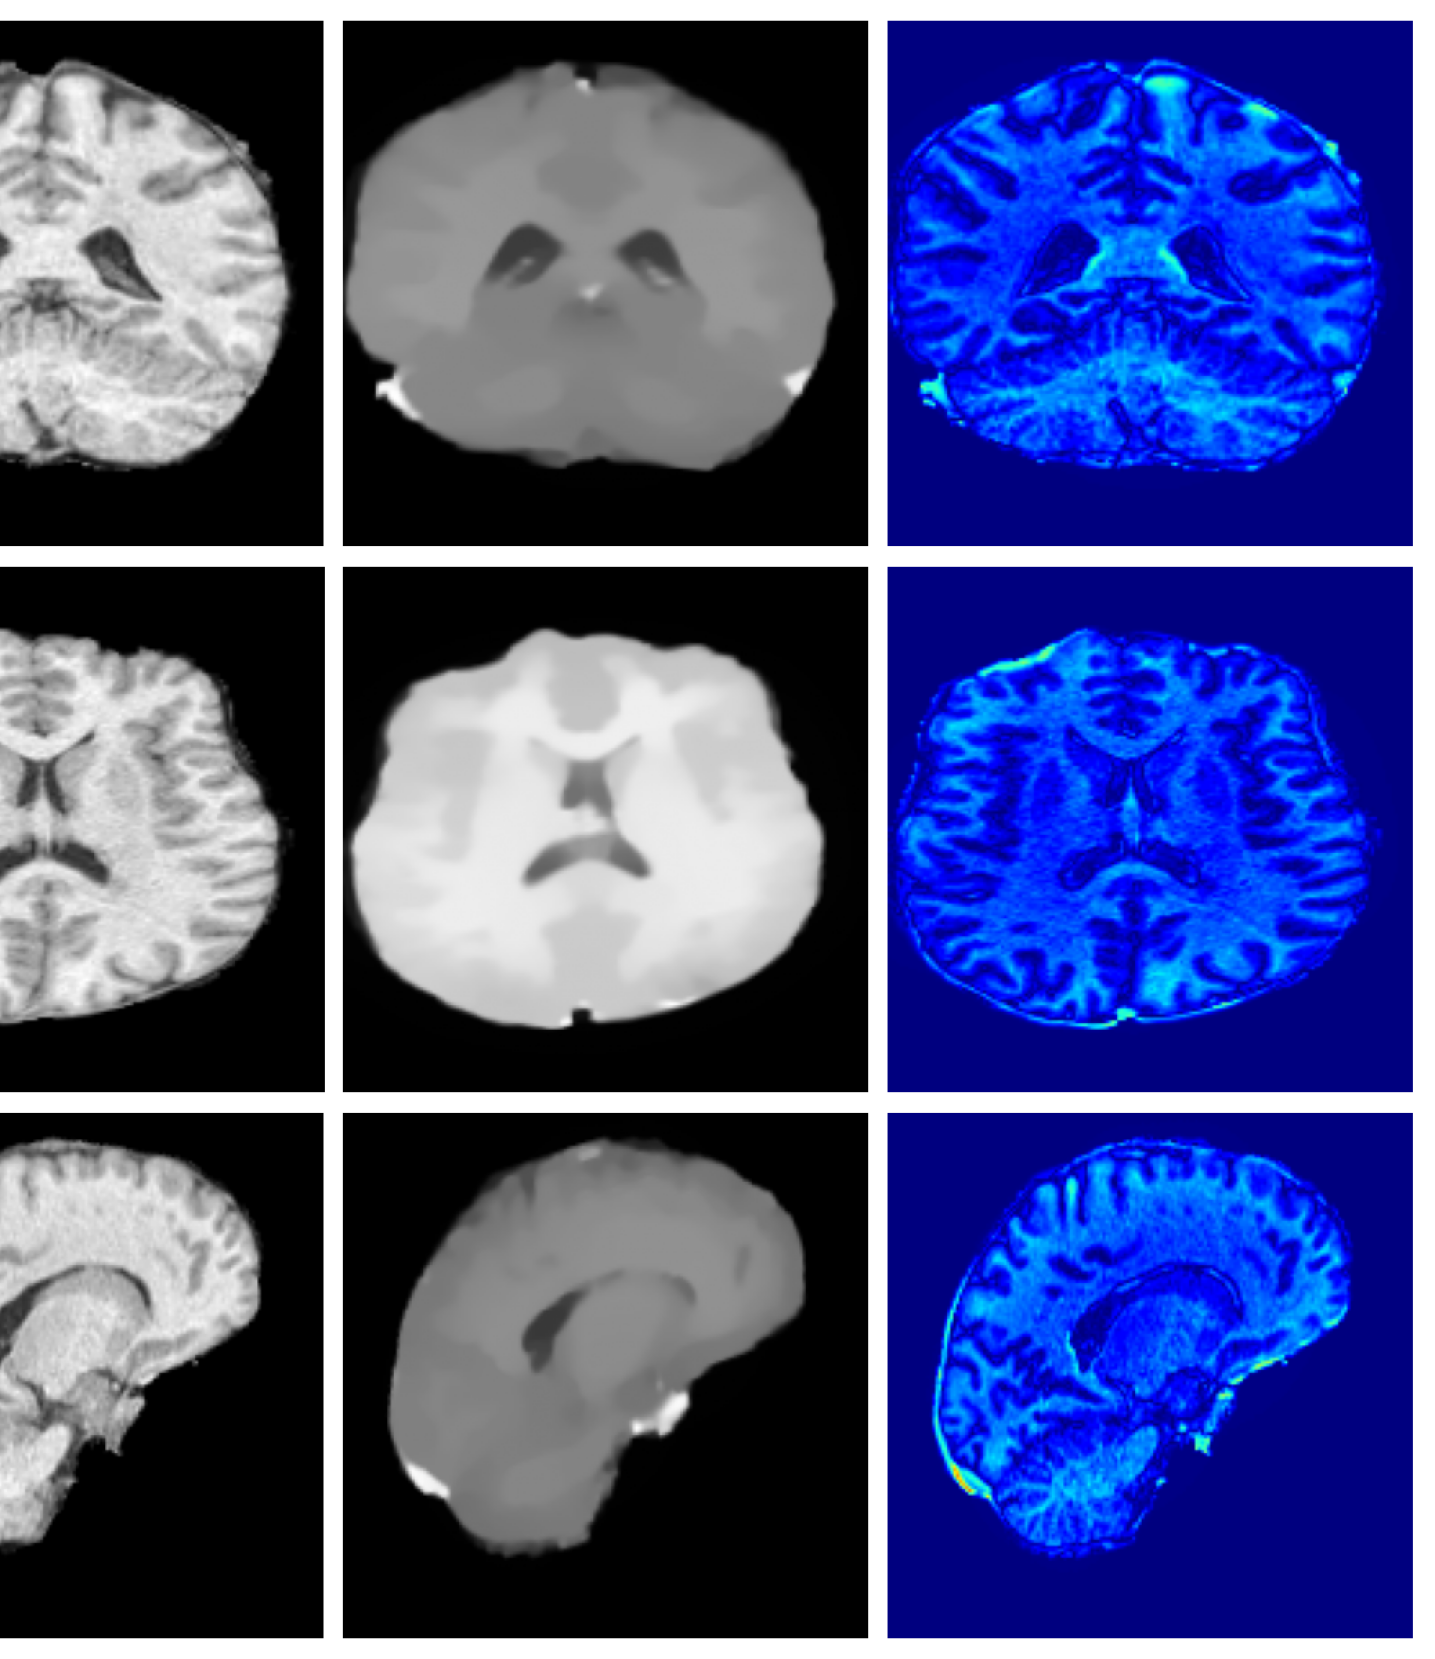

Figure 3 (additional examples in Appendix A.9) shows that SynthSR preserves healthy tissue but struggles with large lesions, while DDPM-2D and DDPM-3D, despite producing high-contrast anomaly maps, generate unrealistic homogeneous inpainting, consistent with their lower performance in Table 3. In contrast, our method yields the most anatomically plausible inpainted regions, although anomaly maps appear subtle due to low contrast between lesions and healthy tissue.

A.9 Additional qualitative inpainting results

Additional qualitative results for the ATLAS and BraTS datasets are given in Figures 12 and 13, respectively.